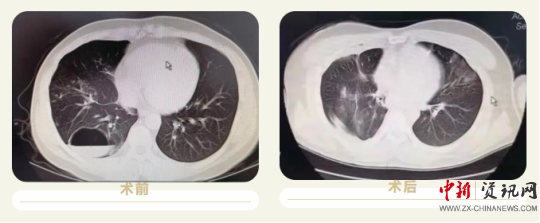

患者董某,男,32歲,因“咳嗽、咳痰伴咯血2天”收入院,患者及家屬敘述于本次入院兩天前受涼后出現(xiàn)咳嗽,咳白色粘液,有咯血,主要為痰中帶血,呈鮮血,量較少,活動(dòng)后氣促,來上蔡縣人民醫(yī)院治療,經(jīng)ct檢查后以“肺囊腫”收住入院,患者病變位置于右肺下葉,手術(shù)切除區(qū)域毗臨心臟及胸腔大血管,同時(shí)該手術(shù)需要全麻,術(shù)中及圍手術(shù)期管理難度大,經(jīng)過上蔡縣人民醫(yī)院神經(jīng)外科團(tuán)隊(duì)及麻醉科主任陳樹軍的充分論證和術(shù)前準(zhǔn)備后決定行胸腔鏡下手術(shù)治療,手術(shù)過程順利,目前患者各項(xiàng)生命體征平穩(wěn),正在康復(fù)中。